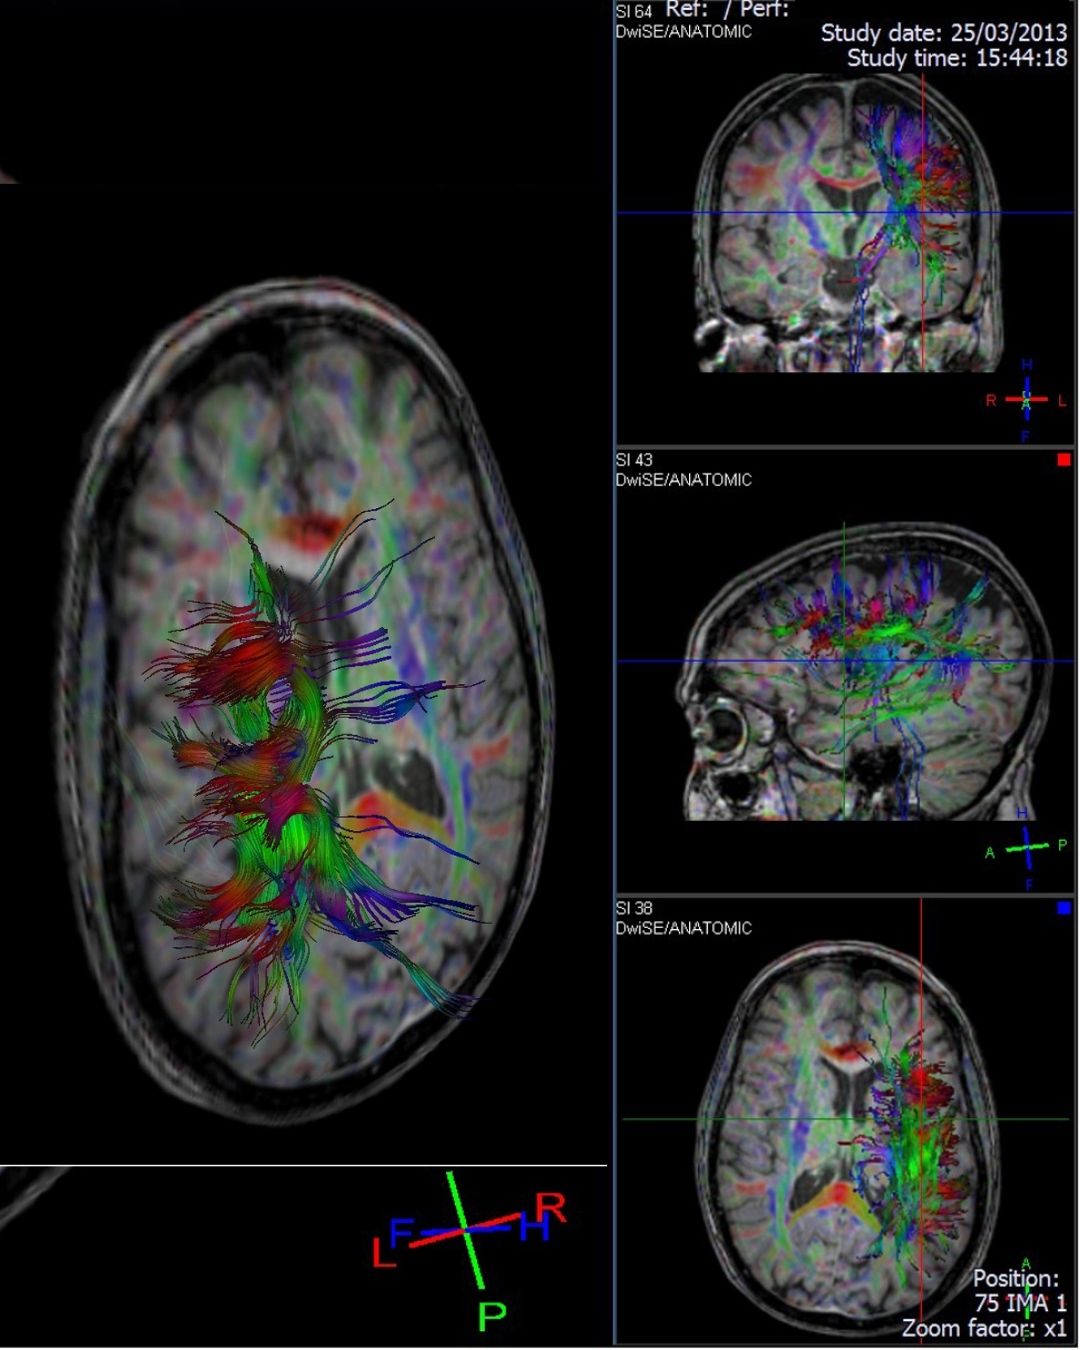

MR Traktografi, manyetik rezonans görüntüleme (MR) teknolojisinin özel bir uygulamasıdır ve beyin veya omurilikteki sinir yollarının (beyin aksonlarının) haritalanmasını sağlar. Daha basit bir ifadeyle, MR Traktografi, beyindeki “sinir yollarının yollarını” 3 boyutlu olarak görselleştirir.

• MR Traktografi, genellikle Diffusion Tensor Imaging (DTI) adı verilen bir MR tekniği kullanır.

• Bu teknik, su moleküllerinin beyin dokusu içindeki hareketini izler. Su molekülleri sinir lifleri boyunca daha kolay hareket ettiği için, bu hareketin yönü sinir yollarının yönünü gösterir.

• Sinir yollarının 3 boyutlu ve ayrıntılı görüntülerini sağlar.

• MR Traktografi doğrudan sinir hücrelerini göstermez, yalnızca su moleküllerinin hareketini takip ederek dolaylı bir harita çıkarır.

• Çok küçük veya karmaşık çapraz sinir yollarında bazı hatalar olabilir.